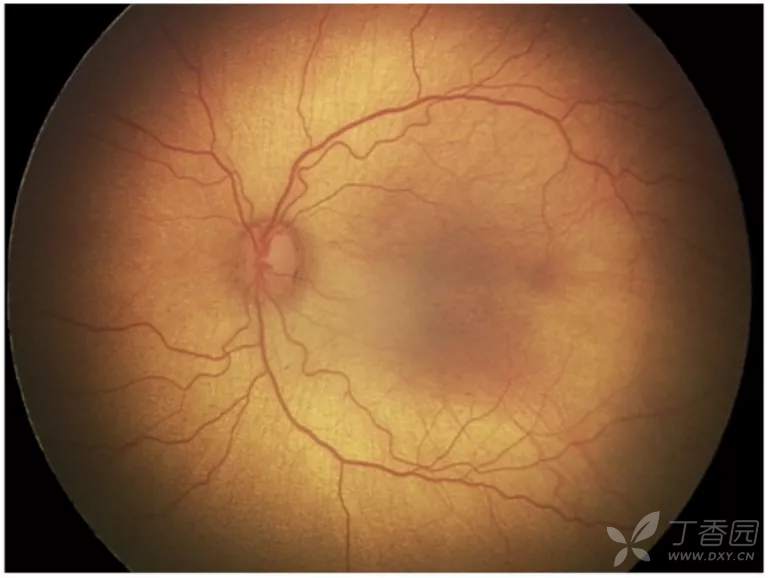

02、plus病变和plus病变前期

plus病变指视网膜血管扩张和迂曲。plus病变前期定义为视网膜血管异常扩张和迂曲,但不足以诊断为plus病变。

图. plus病变前期,动脉明显纡曲,但静脉扩张较轻。